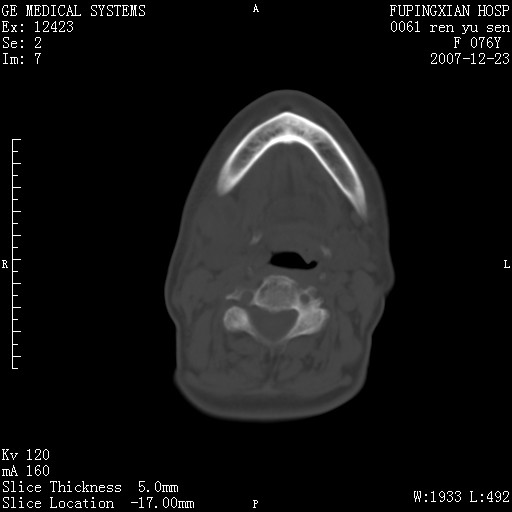

男性 76岁 下颌右侧磨牙区肿物数月, 约2.0*1.5cm大小波及颊舌侧,伴颌下淋巴结肿大。余(-)

右颈部颌下腺前可见一类圆形软组织密度影,密度不均,内见小片坏死区.颌下颈前可见两枚肿大淋巴结影.考虑淋巴结感染可能性大,建议增强扫描..

右侧第四磨牙缺失,局部牙槽骨质破坏,边界欠清晰,同侧颌下及竟不见多发肿大淋巴结显示。考虑肿瘤病变可能性大,感染待排